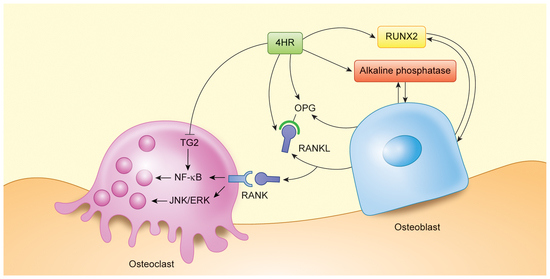

1. Introduction

3.2. 4HR Increased OPG, RANKL, AP, and Runx2 Expression in Tissue

4. Discussion